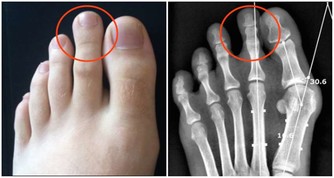

2. 好發頭皮與肘膝:乾癬最常發生在頭皮、手肘、膝蓋等部位,

因為頻繁摩擦,導致皮膚會紅、變厚,而且有屑屑。